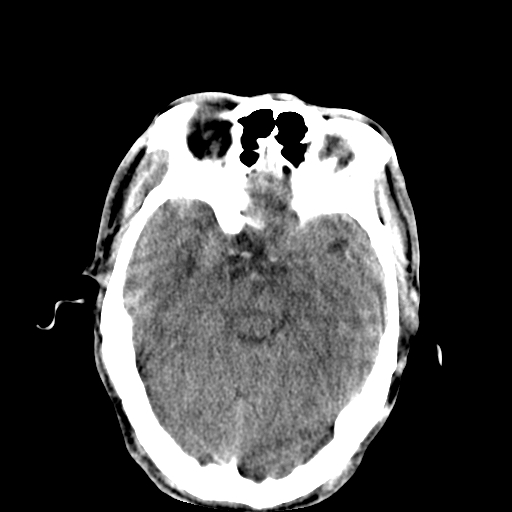

以下是引用李衡钧在2008-9-18 17:37:00的发言:[br]脑质内见两个低密度灶,其内见点状高密度。[br]考虑脑囊虫。建议增强或进一步检查确诊。

以下是引用chmh在2008-9-18 18:45:00的发言:[br]考虑脑囊虫病可能性大,建议行ct增强检查及血清和脑脊液囊虫补体结合试验.